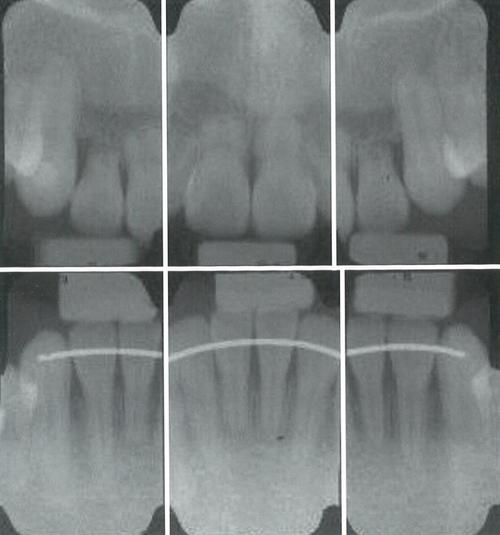

隐形正畸中牙根吸收多为轻度(吸收量<牙根长度的1/3),通常不会影响牙齿功能,但中重度吸收可能导致牙齿松动、牙髓坏死等问题,预防是关键:术前需通过CBCT、根尖片等全面评估牙根状况;治疗中定期拍摄根尖片(每3-6个月一次),监测牙根长度变化;发现吸收迹象后,及时调整矫治方案,如减小矫治力、延长牙齿移动间隔,必要时暂停加力,对于高风险患者,可考虑联合使用药物(如双膦酸盐)抑制破骨细胞活性,但需在医生指导下进行。

A:牙根吸收需通过专业检查发现,如根尖片观察牙根长度变化,CBCT可清晰显示吸收范围,轻度吸收通常无需停止矫正,医生会调整方案(如减小力值、延长复诊间隔);中重度吸收可能需暂停或终止矫正,并联合牙周治疗维护牙齿稳固,具体需根据吸收程度和牙齿状况综合判断。